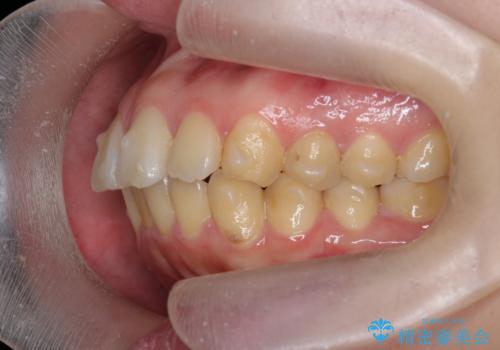

歯を抜かずに行う前歯の角度の改善

- 歯を抜かずに前歯の角度を改善したい、と矯正治療を希望され来院されました。

可及的に前歯部にIPR(歯間の削合)を行い、抜歯をせずマウスピース矯正システムインビザラインで歯の排列を行っていく治療計画としました。

治療の前後を比べると、がたつきや歯の角度が改善したことがしっかりと確認されました。